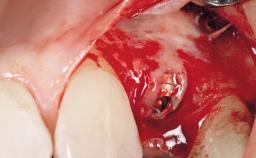

Late Placement of an Implant in a Maxillary Left Central Incisor Site

A 36-year-old female patient was referred for the replacement of the upper left central incisor (tooth 21), which had fractured. Although the tooth had been asymptomatic for many years, the crown began to loosen, at which time she presented to her dentist for an assessment. Teeth 21 and 22 had both been endodontically treated many years previously. She was a healthy individual and a non-smoker.